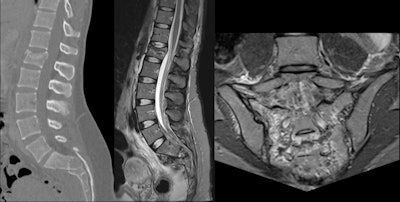

Thoracolumbar spine injuries are more common than cervical spine or sacral lesions. Anterior thoracolumbar abnormalities are a result of excessive loading of the spine, which increases when the athlete is flexed forward. Because elite skiers begin training at an early age, it is likely that the anterior endplate lesions are a result of an imbalance between the applied load and the loading capacity of the immature spine.